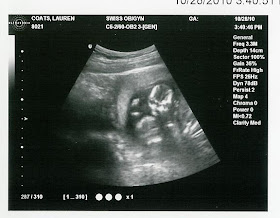

Our appointment today was fantastic! The baby is 14 weeks, 4 days and has grown a ton!! The doctor said everything looks normal and healthy! I think the baby is already cute :)

In the first picture the baby was moving it's arms and legs and the doctor caught the picture right when the leg went in the air. I loved seeing the baby move around - so neat. This is our favorite picture so far! :)